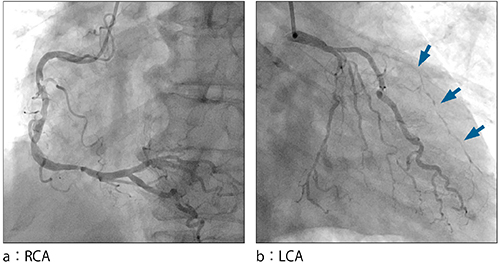

図3 治療前CAG画像

#6に高度狭窄あり。高位側壁枝からの側副血行路でLADが造影されている(←)。